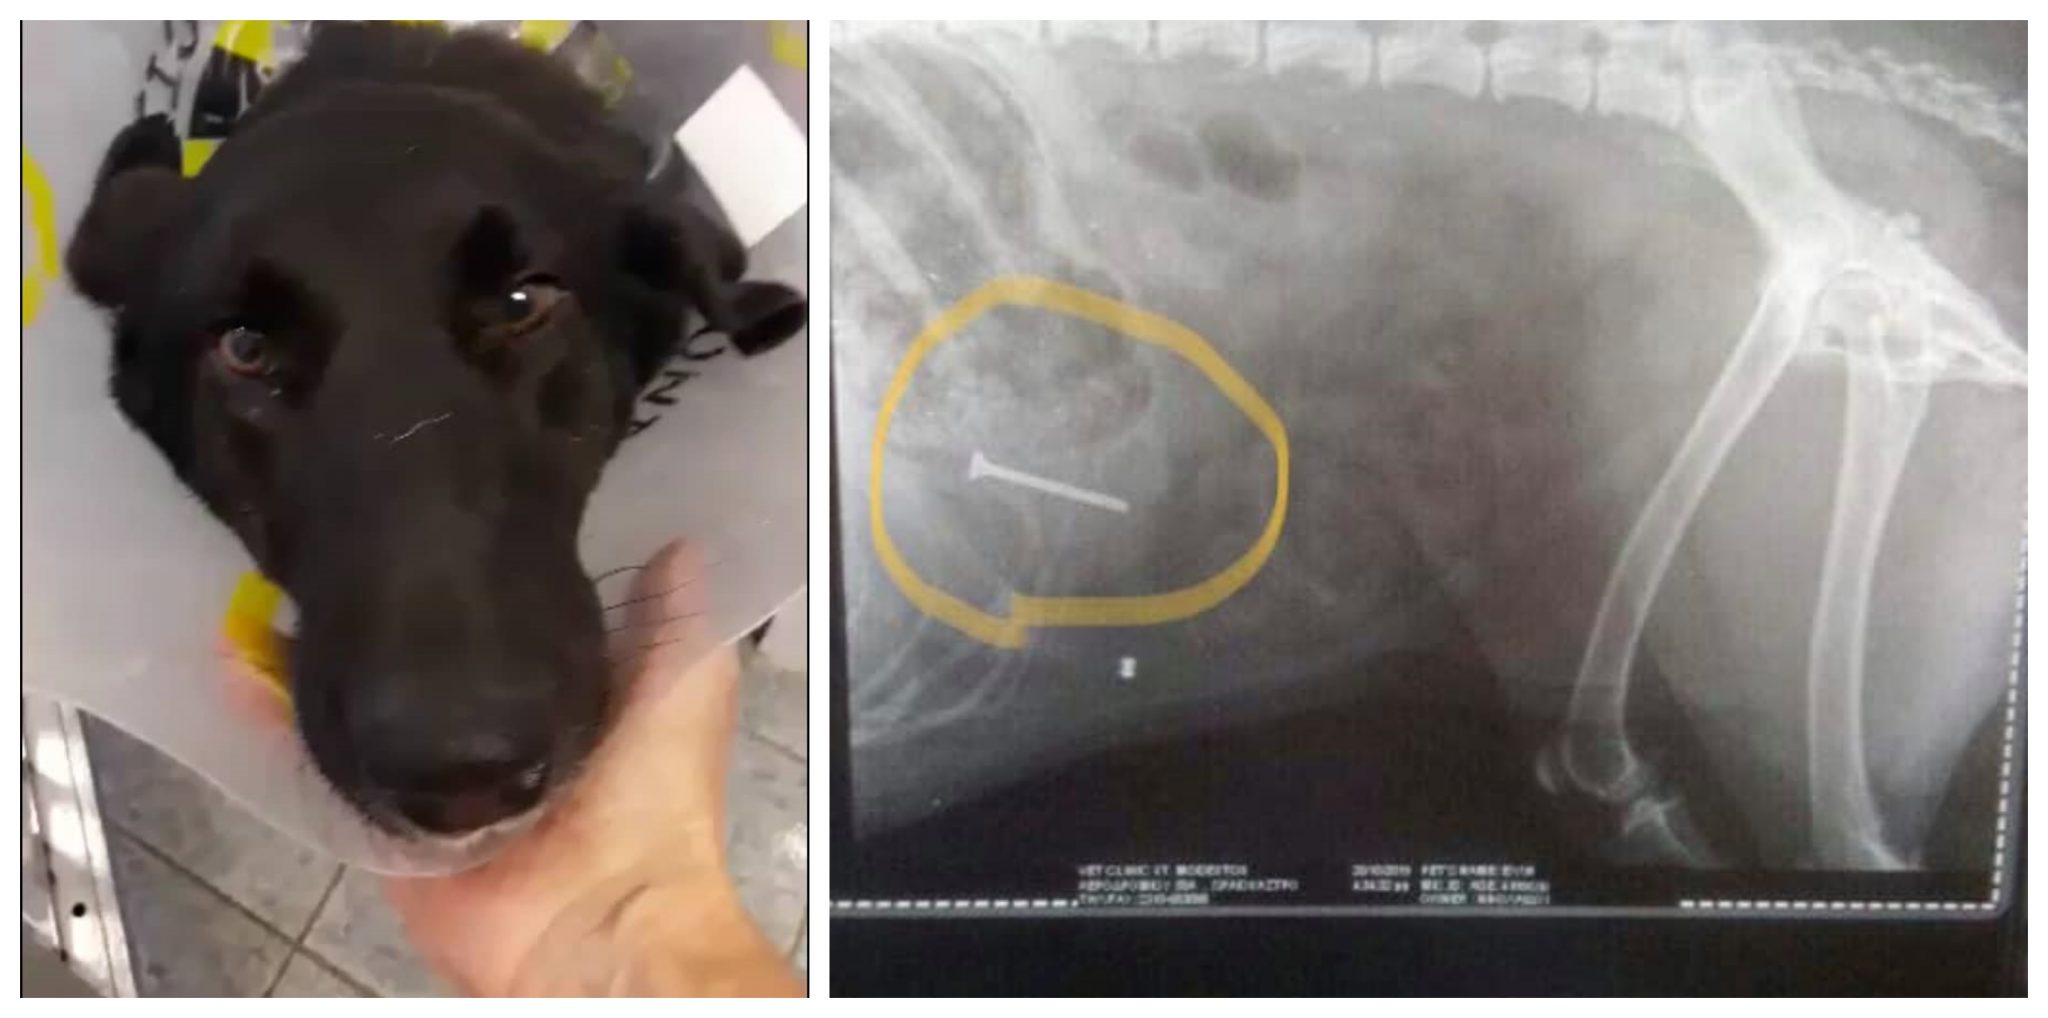

Η σκυλίτσα της φωτογραφίας, από το Κιλκίς, δεν πείραξε κανέναν. Το μόνο της έγκλημα ήταν ότι ήταν αδέσποτη. Κάποιος αποφάσισε να τη σκοτώσει και της έριξε λουκάνικα ή σαλάμι ή κάτι άλλο που μέσα είχαν καρφιά. Χωρίς καμιά τύψη για το πόσο βασανιστικά θα πεθάνει.

Ήταν όμως τυχερή μέσα στην ατυχία της καθώς οι εθελοντές του Φιλοζωικού Συλλόγου Κιλκίς, Φίλοι Αδέσποτων Ζώων Κιλκίς Kilkis Stray Paws Non Profit Organization https://www.facebook.com/KilkisStrayPawsNonProfitOrganization/ που την ταϊζουν τη βρήκαν σε άσχημη κατάσταση και την πήγαν αμέσως στο κτηνιατρείο. Στην ακτινογραφία φάνηκε το καρφί.

Αυτή τη στιγμή βρίσκεται στην κλινική Άγιος Μοδέστος στη Θεσσαλονίκη και κάνουν έκκληση όποιος θέλει να βοηθήσει στο χειρουργείο της.